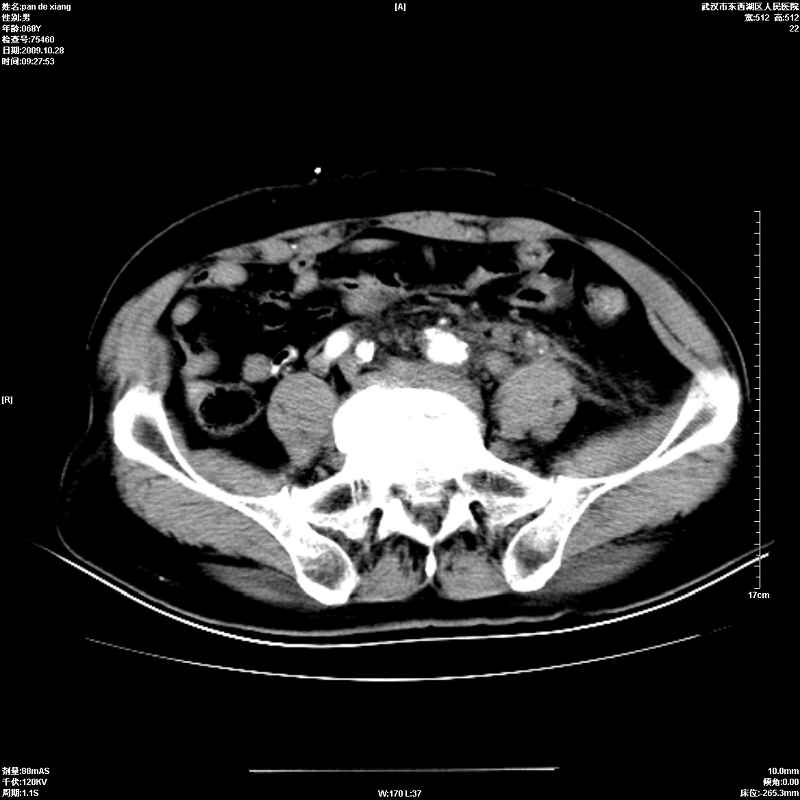

以下是引用杀毒软件在2009-10-28 20:41:00的发言:[br]结合临床考虑---白血病双肾改变或淋巴瘤。

以下是引用zxl51642在2009-10-29 9:59:00的发言:[br]结合临床“单克隆免疫球蛋白血症”,考虑双肾为继发损害并肾功能不全(尿中大量igg及少量iga、igm等大分子免疫球蛋白滤出所致继发损害),椎前软组织肿块为髓外造血。与浆细胞瘤有区别,平扫时有战友说的很清楚。